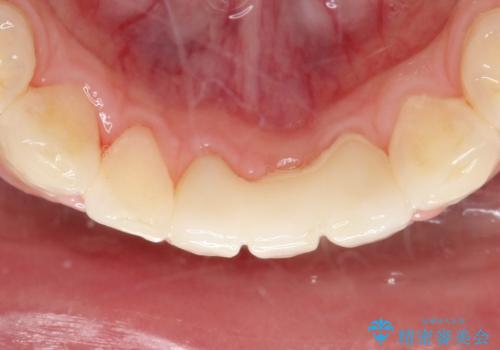

- 晩期残存した下顎乳中切歯の変色を主訴に来院されました。

後続永久歯は先天性欠如しており、下顎前歯のブリッジにて補綴治療を行なっております。